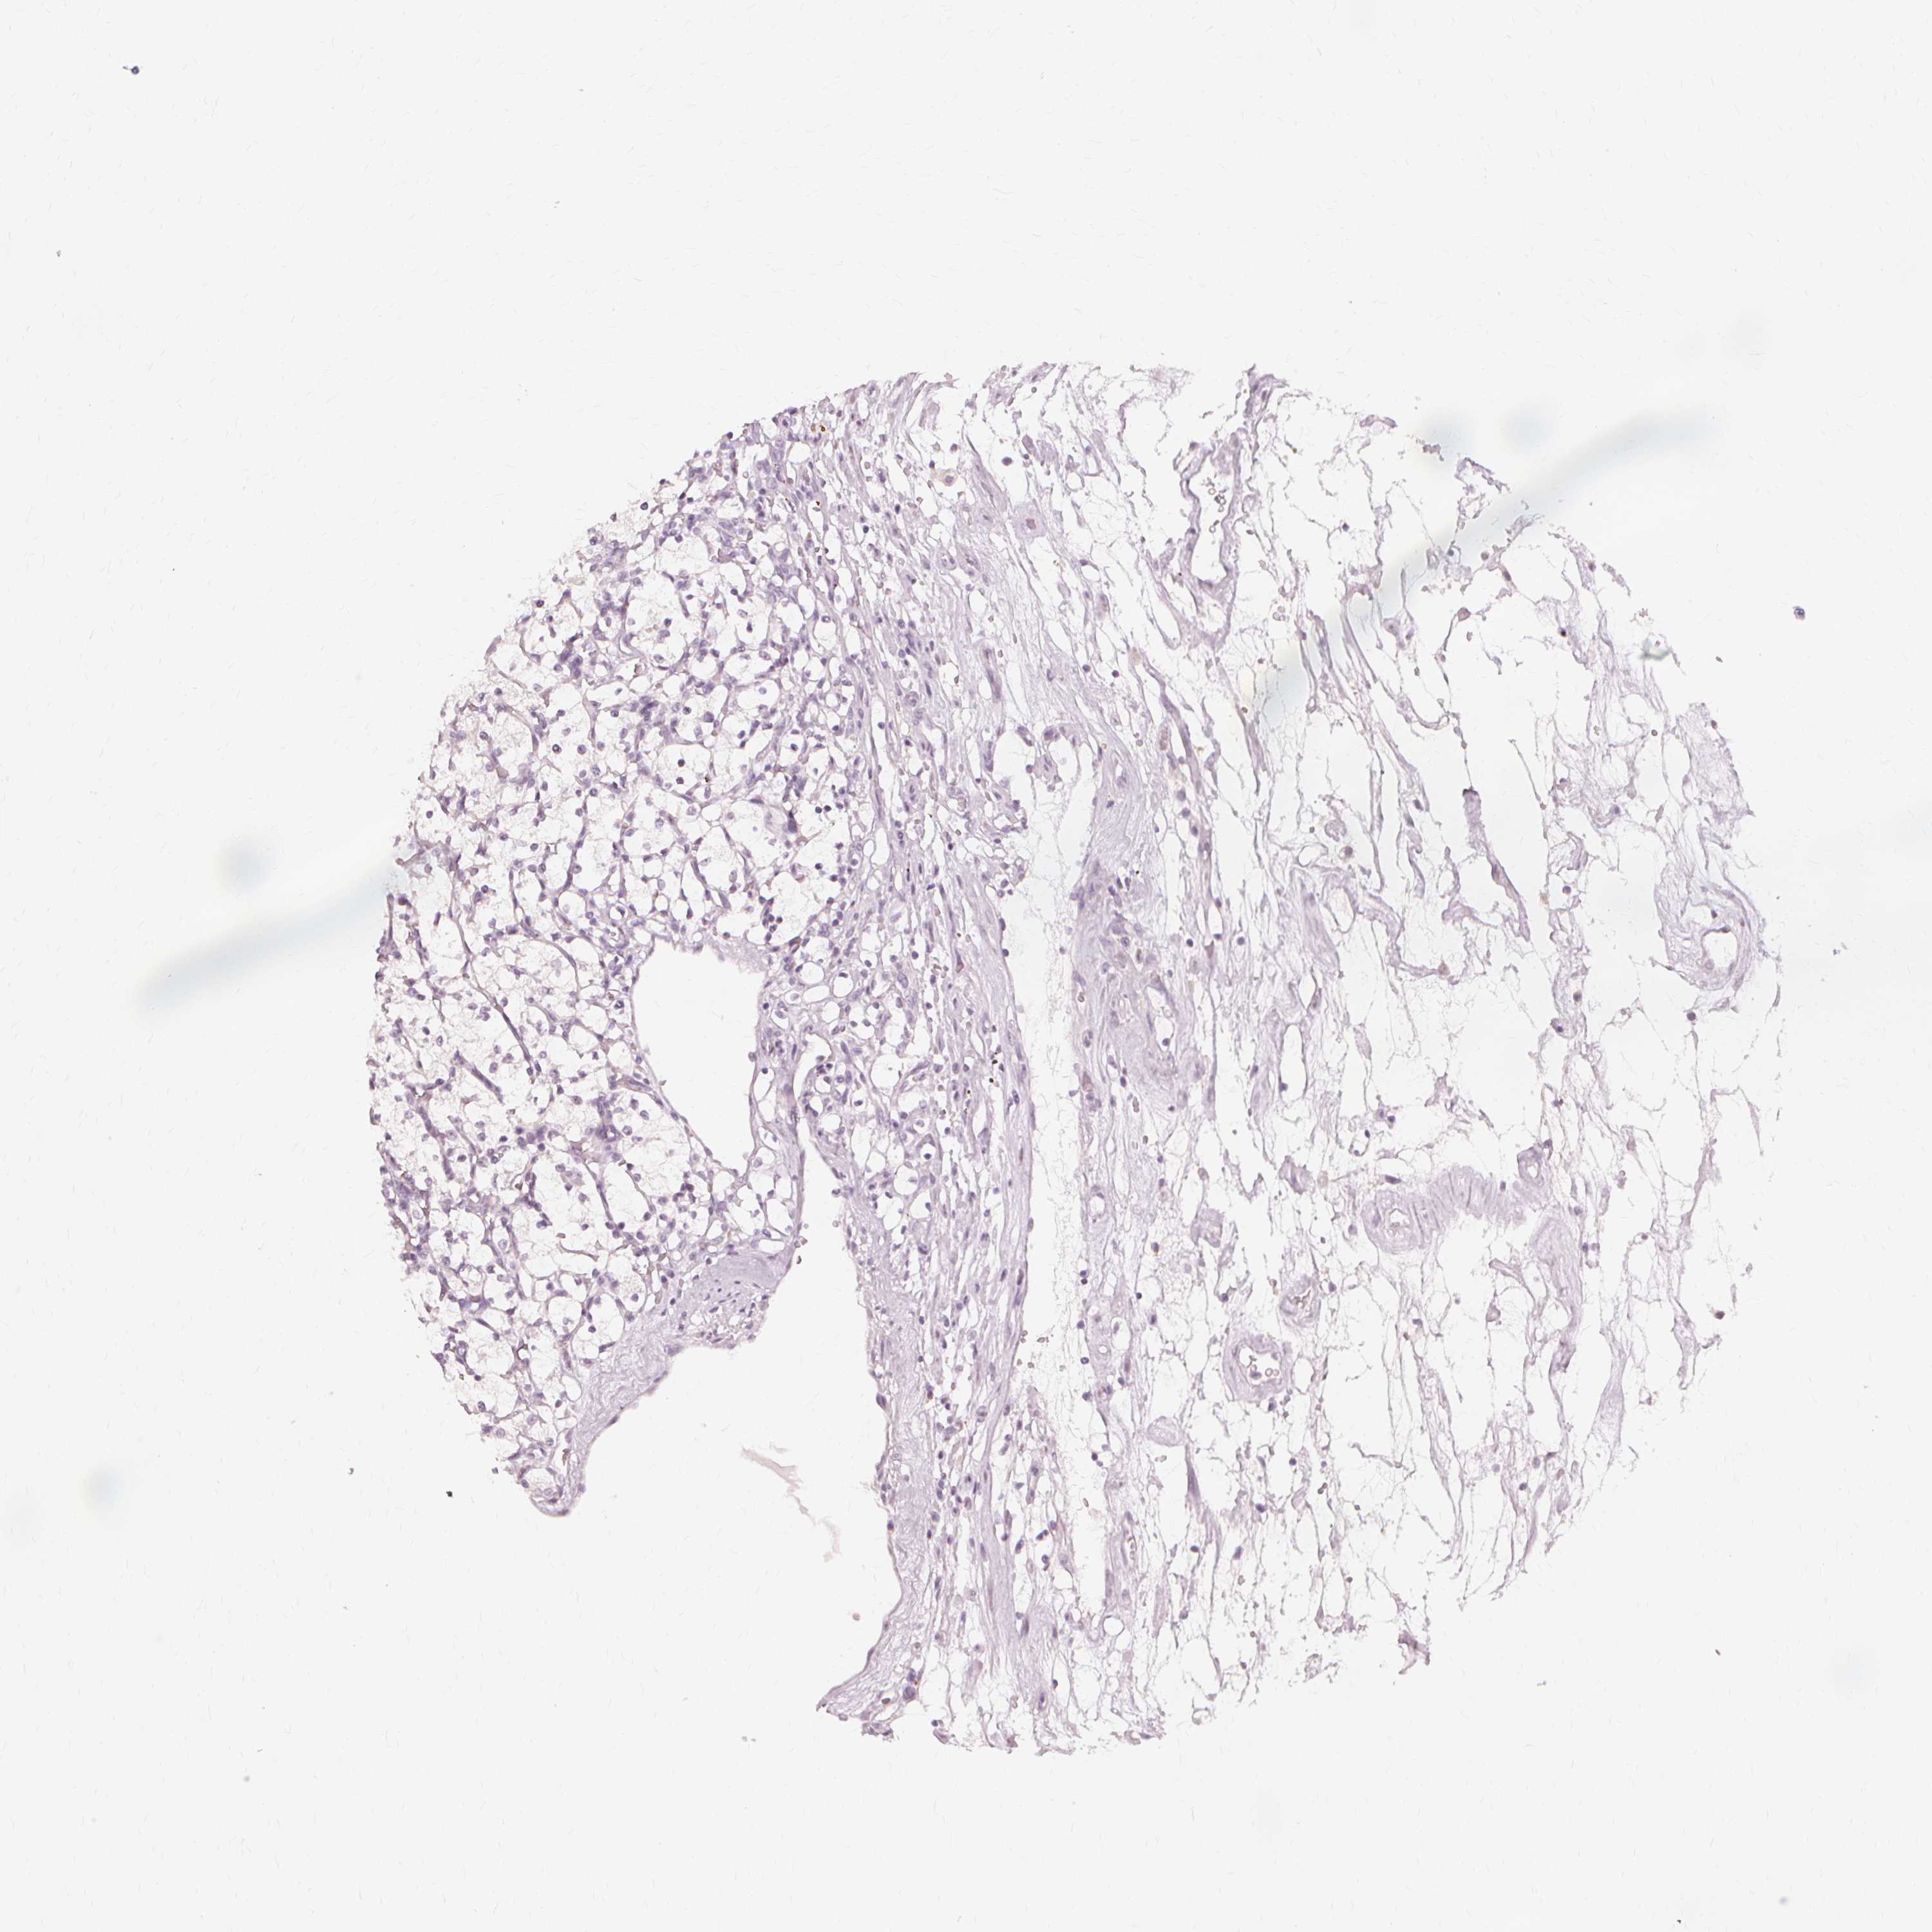

KIDNEY RENAL PAPILLARY CELL CARCINOMA (TCGA) - Interactive survival scatter ploti

The Survival Scatter plot shows the clinical status (i.e. dead or alive) for all individuals in the patient cohort, based on the same data that underlies the corresponding Kaplan-Meier plots. Patients that are alive at last time for follow-up are shown in blue and patients who have died during the study are shown in red.

The x-axis shows the expression levels (FPKM) of the investigated gene in the tumor tissue at the time of diagnosis. The y-axis shows the follow-up time after diagnosis (years). Both axes are complimented with kernel density curves demonstrating the data density over the axes. The top density plot shows the expression levels (FPKM) distribution among dead (red) and alive patients (blue). The right density plot shows the data density of the survived years of dead patients with high and low expression levels respectively, stratified using the cutoff indicated by the vertical dashed line through the Survival Scatter plot. This cutoff is automatically defined based on the FPKM cutoff that minimizes the p-score. The cutoff can be changed by dragging the vertical line or by entering a cutoff value in the square labeled "Current cut-off".

Under the Survival Scatter plot the p-score landscape (black curve; left axis) is shown together with dead median separation (red curve; right axis). Dead median separation is the difference in median mRNA expression between patients who have died with high and low expression, respectively. It is calculated as follows: median FPKM expression of dead patients with high expression - median FPKM expression of dead patients with low expression. This is intended to aid the user in visually exploring custom cutoffs and the associated p-scores and dead median separation.

Individual patient data is displayed and can be filtered by clicking on one or more of the category buttons on the top of the page. Categories describing expression level and patient information include: high, low, alive, dead, female, male and tumor stages. The scale of the x-axis can be toggled between linear and log-scale by clicking on the "x log" button. Mouse-over function shows TCGA ID, patient information and mRNA expression (FPKM) for each patient.

& Survival analysisi

Kaplan-Meier plots summarize results from analysis of correlation between mRNA expression level and patient survival. Patients were divided based on level of expression into one of the two groups "low" (under cut off) or "high" (over cut off). X-axis shows time for survival (years) and y-axis shows the probability of survival, where 1.0 corresponds to 100 percent.

Survival analysis data not available.

TCGA RNA samplesi

RNA-seq data is reported as average FPKM (number Fragments Per Kilobase of exon per Million reads), generated by the The Cancer Genome Atlas (TCGA) .

Normal distribution across the dataset is visualized with box plots, shown as median and 25th and 75th percentiles. Points are displayed as outliers if they are above or below 1.5 times the interquartile range. FPKM values of the individual samples are presented next to the box plot.

Average pTPM 0.0

Number of samples 282